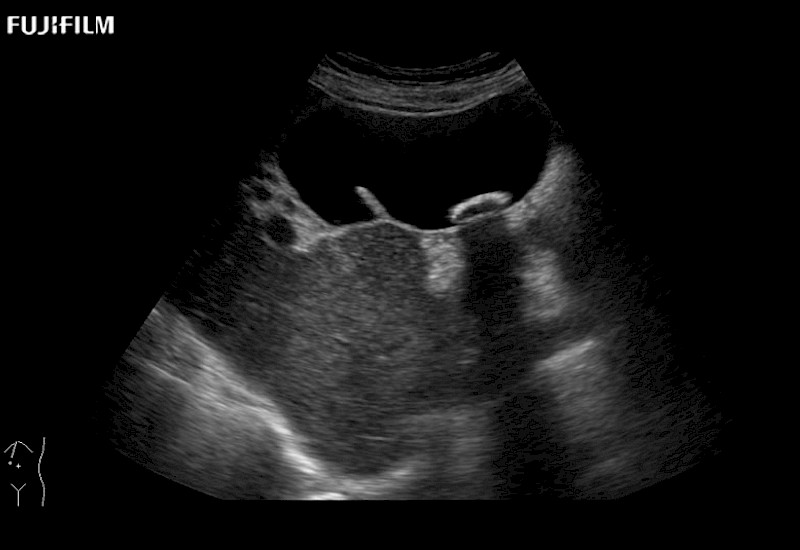

for use during general and laparoscopic procedures: Tumor localization & staging, Ablation, Resection, Biopsy, Transplant, Abdominal exploration, Robotic surgery

Our dedication to Laparoscopic Surgery allows us to offer superior image quality, outstanding system reliability and intuitive use of cutting edge technology.